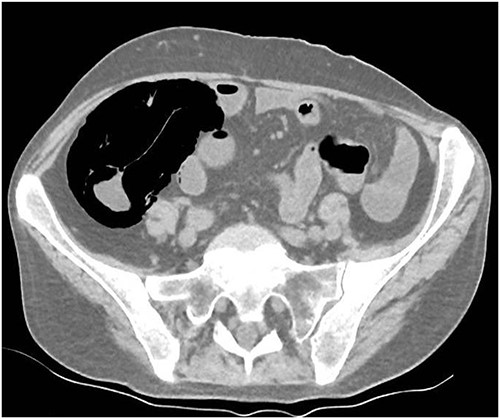

A 49-year-old female with a background of stage IV diffuse large B-cell lymphoma and subsequent graft-versus-host disease from a bone marrow transplant presented to a rural hospital in New South Wales, Australia with 12-h history of painless per rectal bleeding and fever. On examination she had a soft, but distended abdomen. Laboratory investigations revealed thrombocytopenia and hypokalaemia. Computed tomography of the abdomen and pelvis had a bizarre appearance due to pneumatosis cystoides coli extending from the ileocaecal junction to the mid-transverse colon. Given her benign abdominal examination, her management was initially supportive with intravenous antibiotics, intravenous fluid resuscitation and correction of electrolyte abnormalities.

A 49-year-old female with a background of stage IV diffuse large B-cell lymphoma and subsequent chronic graft-versus-host disease (cGVHD) from a bone marrow transplant presented to a rural referral hospital in New South Wales with a 12-h history of painless per rectal bleeding and fever. She had undergone her last cycle of chemotherapy 12 months prior and her cGVHD was being treated with dexamethasone mouthwash, oral cyclosporine and an infusion of rituximab, administered the day prior to this presentation. On examination she had a soft, but distended abdomen. Laboratory investigations revealed thrombocytopenia and hypokalaemia. Computed tomography (CT) of the abdomen and pelvis had a bizarre appearance due to pneumatosis cystoides coli extending from the ileocaecal junction to the mid-transverse colon (Figs 1–3). A chest X-ray was also taken, which shows evidence transmural air within the ascending colon, including the hepatic junction (Fig. 4). Given her benign abdominal examination, her management was initially supportive with intravenous antibiotics, intravenous fluid resuscitation and correction of electrolyte abnormalities. She was subsequently transferred to a metropolitan tertiary hospital, under her usual treating haematologist with consultation by the colorectal surgical team. She recovered and did not require any acute surgical intervention for pneumatosis cystoides coli.